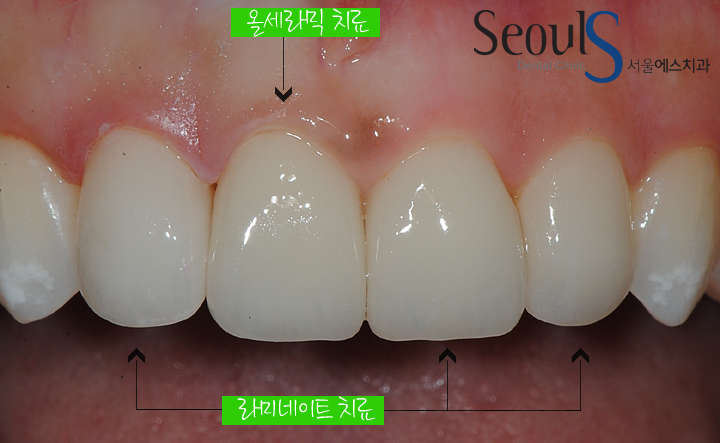

현재 상태에서는 올세라믹 치료로 가지런하고 하얀 치아가 가능한데요

치료 전에 깨졌던 앞니는 올세라믹 치료를 계획했고

나머지 치아는 치아 표면을 다듬고 라미네이트로 치료 할 예정입니다

라미네이트+올세라믹 치료 후 모습입니다

예쁘게 치료가 마무리 된 모습입니다

삐뚤고 얼룩이 있는 앞니 부분교정 후 라미네이트와 올세라믹으로 치료한 모습입니다

V자 형태로 앞니가 삐뚤었는데 부분 교정 후 라미네이트로 치료를 마친 모습입니다